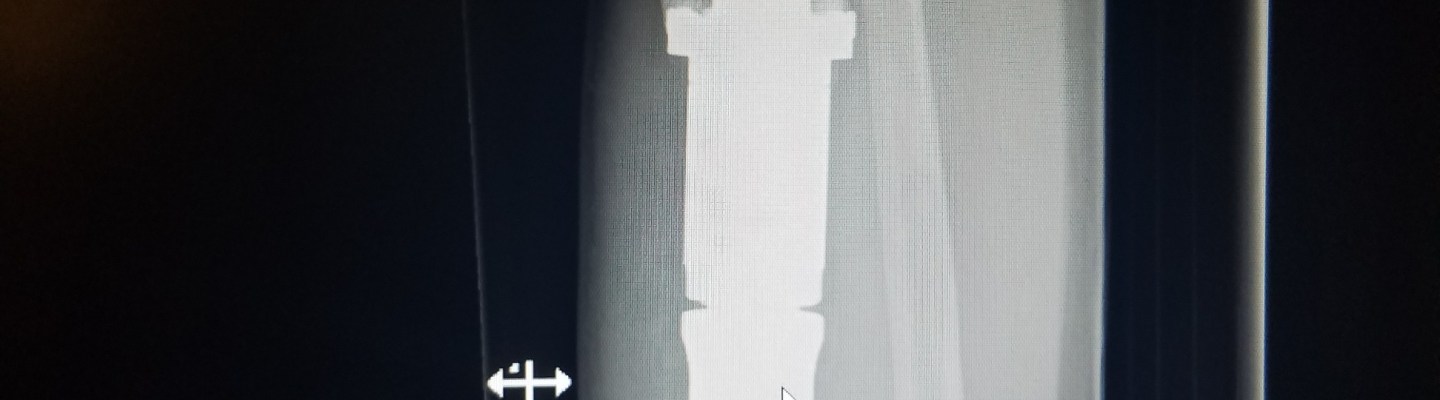

Remember that cool implant in Greg’s leg? Today he heard a “pop” and then this happened. It is past midnight and we still don’t have answers… so stay tuned for the rest of the story.